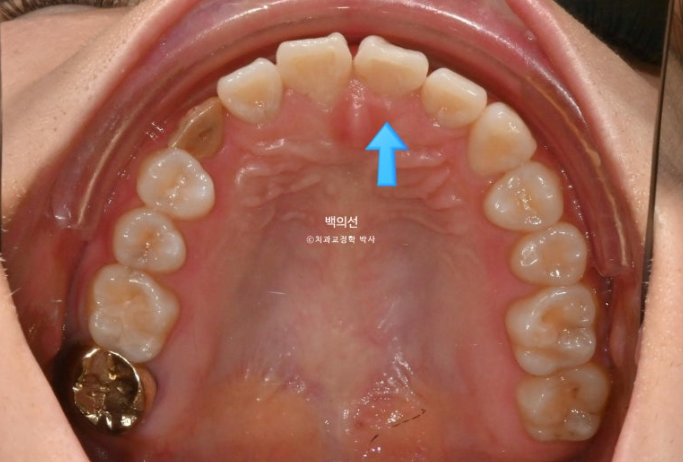

오래 전 했던 교정으로 어금니 교합은 나쁘지 않은 상태입니다.

인비절라인 라이트로 앞니 배열과 뿌리를 뼛속으로 깊이 넣어주는 치료를 권유드렸습니다.

또한 블랙트라이앵글 사이즈를 줄이기 위한 치간삭제도 계획하기로 했습니다.

위 앞니가 한쪽으로 기울어져 있는데다가 한쪽 송곳니가 안보이니 앞니 교합평면 기울어짐이 심해보입니다. 캔팅이라고 하죠.

이런 부분까지 개선되도록 치료계획에 반영됩니다.